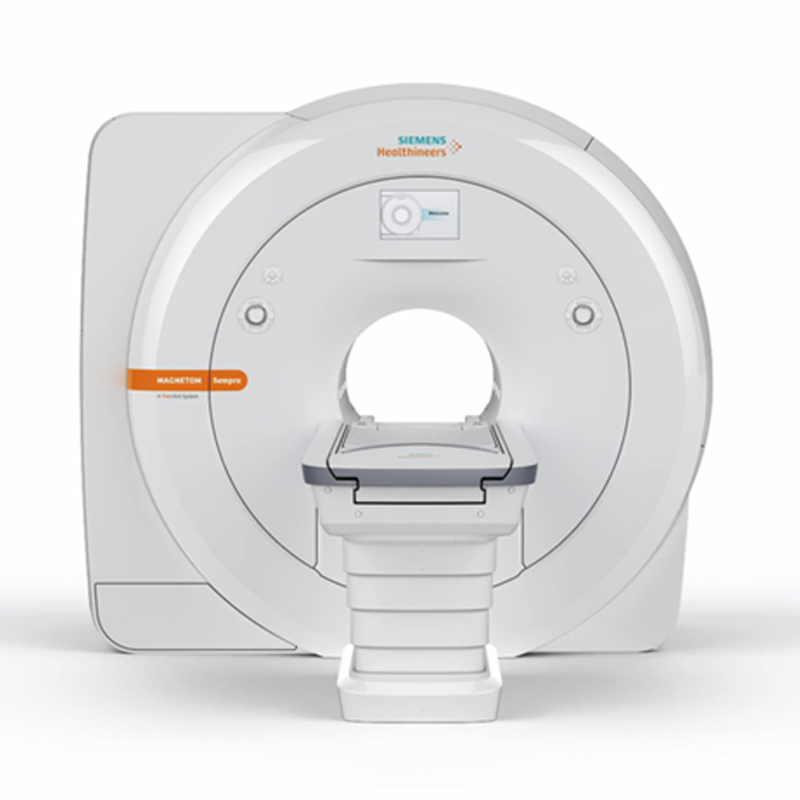

Full Dijital Yapay Zeka Destekli Son Teknoloji 3 Tesla MR Hastalıkta ve Sağlıkta Yanınızdayız

3 TESLA MR YAPAY ZEKA DESTEKLİ

3 Tesla MR’ın Avantajları

3 Tesla MR Tüm Vücut Görüntülemede Yapay Zeka Destekli Son Teknoloji